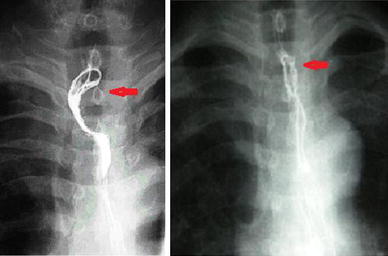

Upper esophageal carcinoma with local advance downstaged effectively after neoadjuvant chemotherapy (the right picture was taken before neoadjuvant chemotherapy; the left one after neoadjuvant chemotherapy)

For a long period of time, the transhiatal esophagectomy has been regarded as a controversial procedure because of failure to do extensive lymphadenectomy. In order to try to decrease the possible influence of inadequate lymph-node dissection, patients undergoing LTE in this study received neoadjuvant and adjuvant chemotherapy. It is uncertain whether neoadjuvant chemotherapy followed by esophagectomy might lead to greater long-term survival [17, 18, 19]. But survival analysis by Kaplan–Meier’s method demonstrated that overall survival and disease-free survival in Group 1 seem to be similar to those in Group 2. The median overall survival of Group 1 and Group 2 reached up to 30.8 and 27.2 months, respectively (P = 0.962). Furthermore, neoadjuvant chemotherapy effectively downstaging esophageal carcinoma with local advance was observed in 11 cases. Downstaging these tumors made them more resectable.